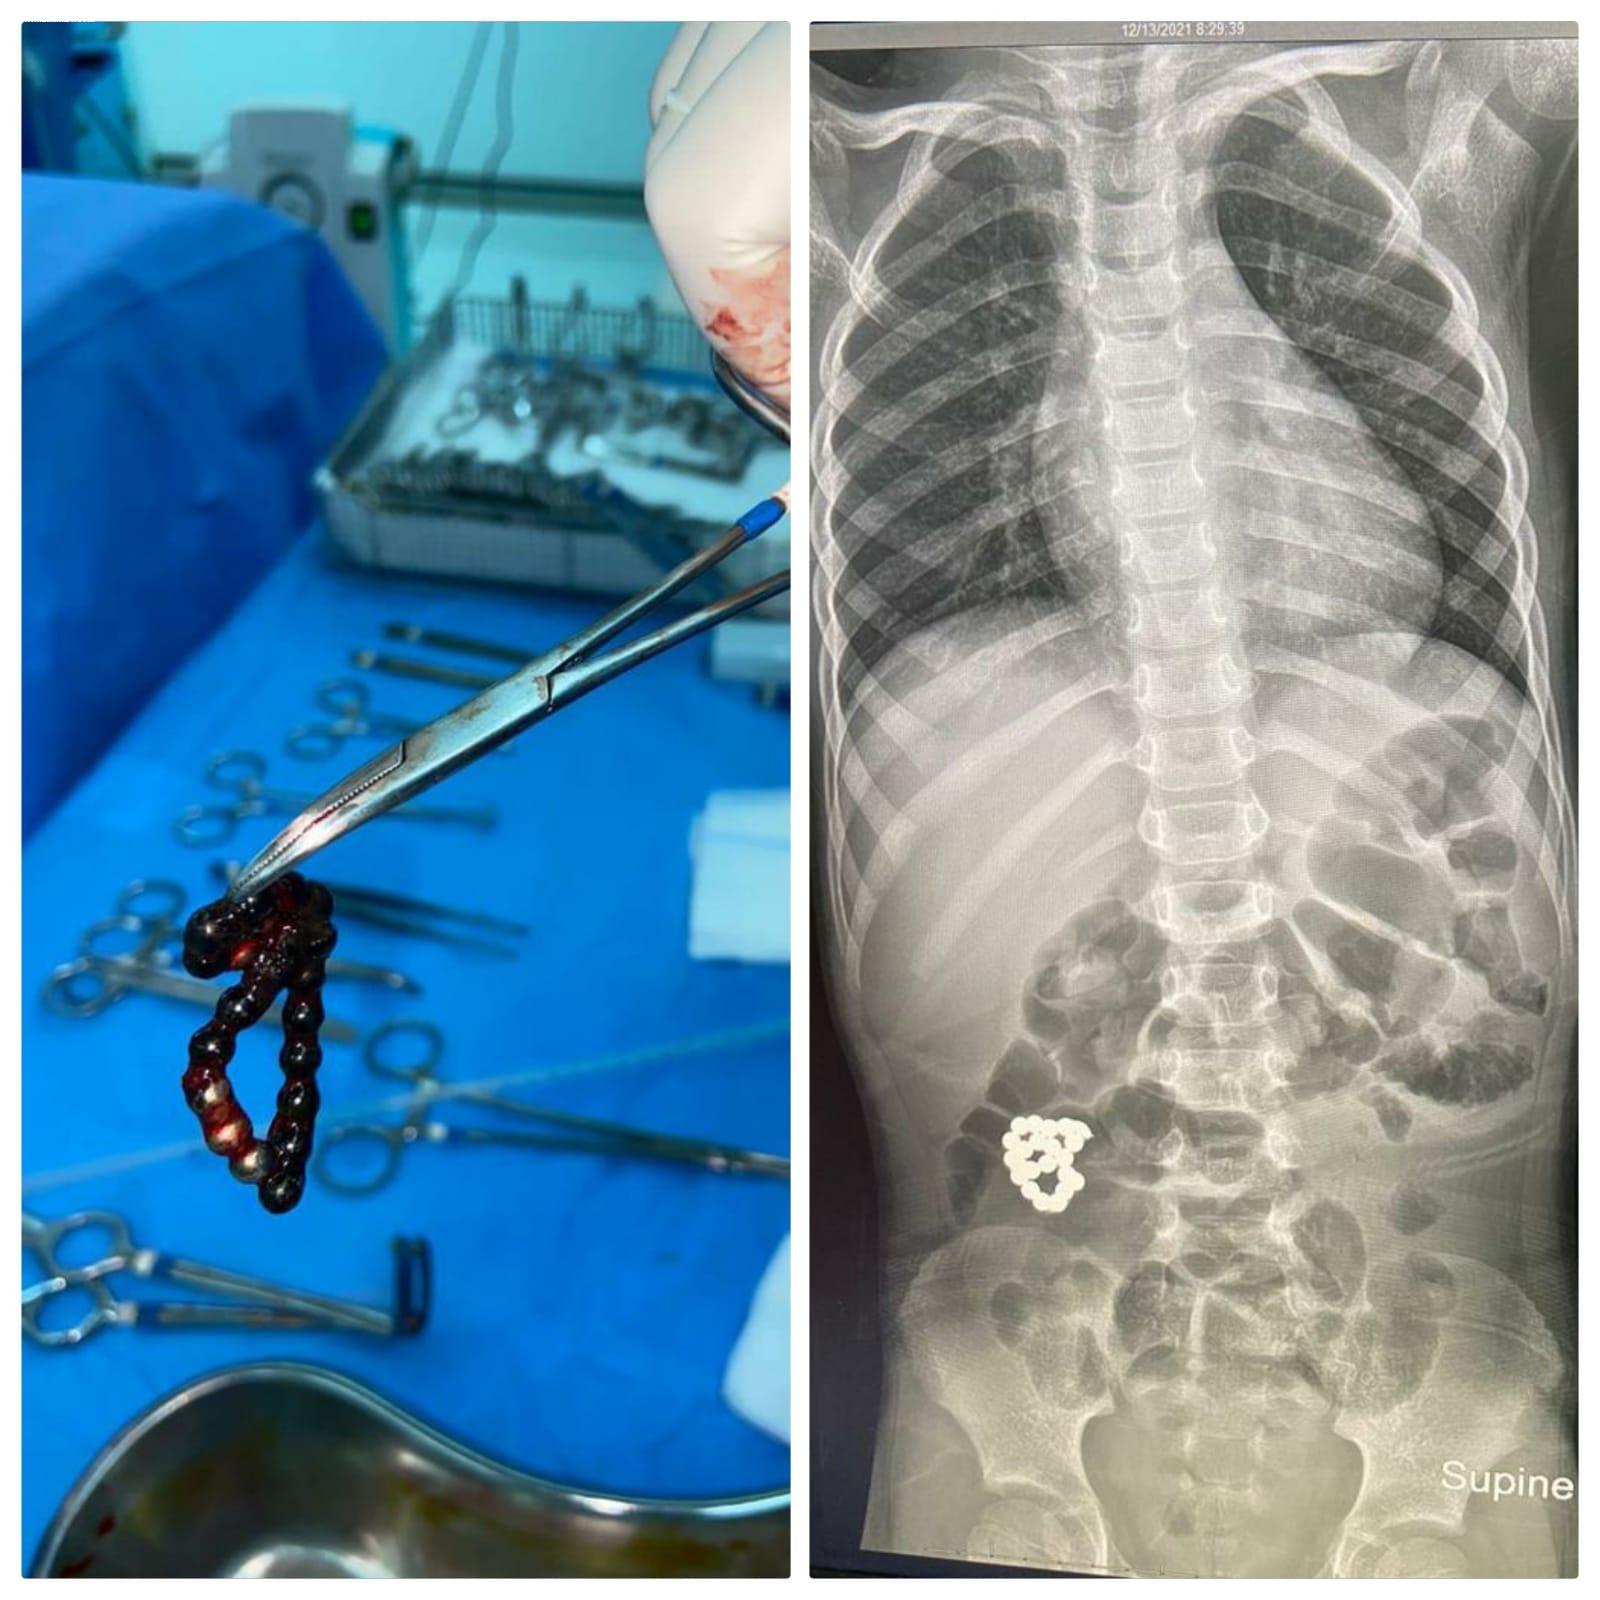

تمكن فريق طبي بمستشفى الملك عبد العزيز بجدة بقيادة بروفيسور جراحة الأطفال الدكتور عمر منصور من إنقاذ حياة طفل في السادسة من عمره ، حضر لطوارئ المستشفى يشتكي من ألم في البطن ملازمه منذ ٤ أيام و ازدادت الآلام مع الوقت ، حيث تم عمل الفحوصات اللازمة ، و أظهرت صور الأشعة وجود جسم غريب في الأمعاء .

و على الفور تم إدخال الطفل لغرفة العمليات واستخراج الجسم الغريب ، كما تضرر جدار الأمعاء ، حيث تم استئصال الأجزاء المتضررة في عملية أستغرقت ساعتين و نصف تكللت بالنجاح و لله الحمد و الطفل في حالة مستقرة بفضل الله ، في قسم التنويم العادي و حالته في تحسن .